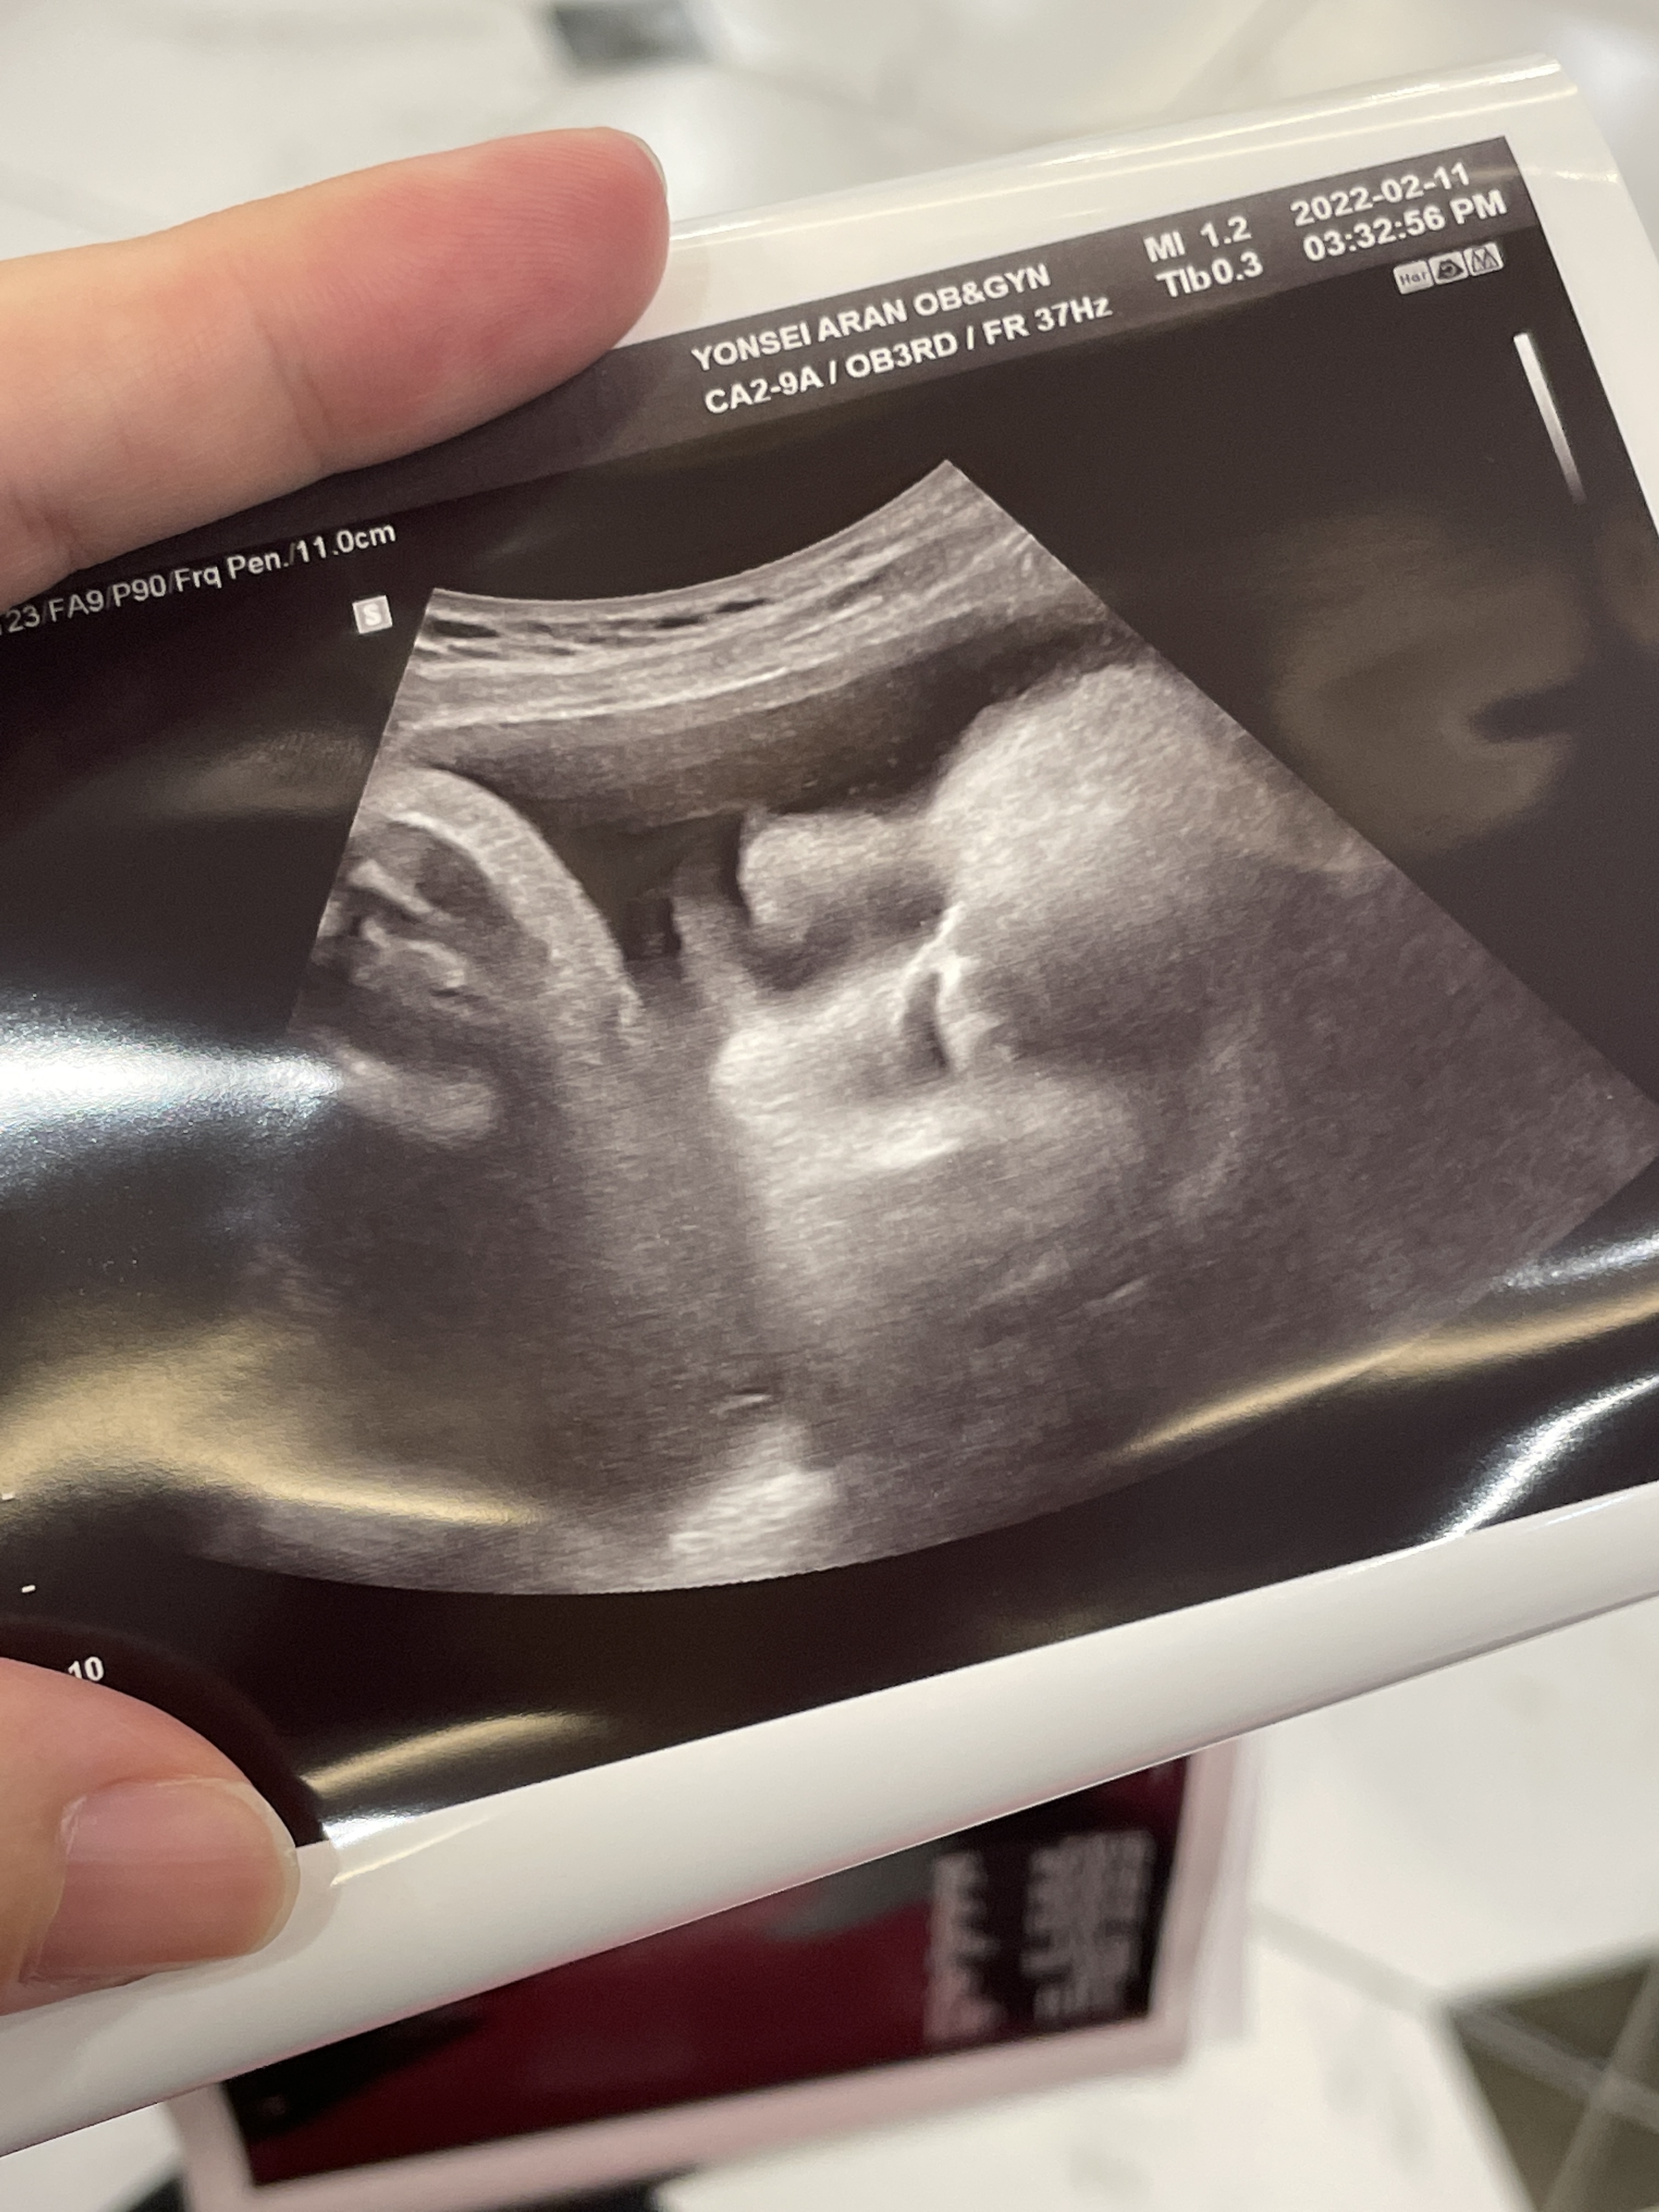

37주 1일차 진료

35주에 진료를 보고 2주만에 진료를 봤다.

머리가..쑥쑥 크고있었다.

몸무게는 딱 주수에 맞는데

머리크기만 3주나 앞서나갔다..

38주에 내진하자고 하셨는데 머리크기 보시고